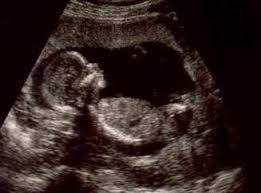

Девочки, подскажите, к Белоусовой можно встать на учет, если я не с ее участка? Мне в регистратуре надо договариваться или непосредственно с ней? И еще, на УЗИ первом есть возможность записать видео, фото на флешку? Муж в долгосрочной командировке, хотелось бы порадовать его. К кому пойти на УЗИ , чтоб не отказали ? Спасибо большое!

да нет, Дрозд записывает и на флешку, но самую древнюю нужно искать, на 32Мб - проще диск купить CD-R

качество изображения на аппаратуре, с которой работает Дрозд не фонтан

начитавшись о том, что девчонки видят, как ребенок гримасничает, я была очень расстроена, когда увидела размытое изображение своего дитя(( гениталии только увидела после того, как изображение ооочень увеличили (на весь экран), а об улыбке, волосах и тд молчу - на фотках, которые нам скинули, еле можно разобрать, где ребенок